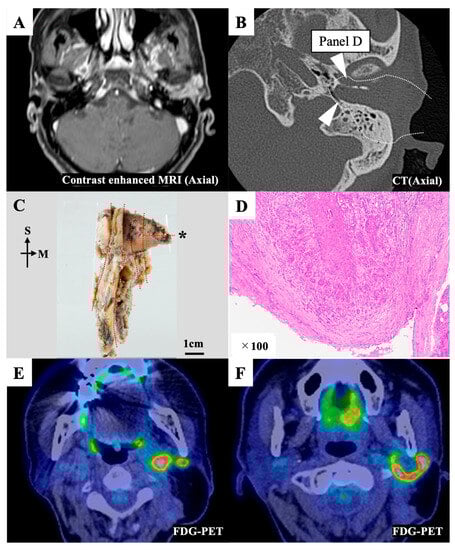

3.2.2. Case 11

| 11 | Surgery * | cLTBR | 2 | 2 b | m3 | 0 | 1, 0, 1 | + | + | N | |||||||||||||||||